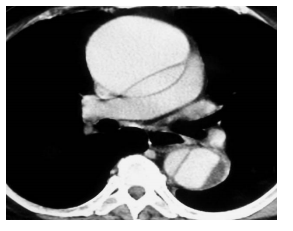

Homem, 48 anos, apresenta quadro súbito de dor torácica anterior em rasgada com

irradiação dorsal associado à sudorese e mal-estar. De base tabagista, etilista e portador de

hipertensão arterial sistêmica em tratamento

irregular. Ao exame físico, encontrava-se sudoréico,

pálido e com PA 220 x 120 mmhg, P 120 bpm, FR

28 irpm e SAT 92% em ar ambiente. ECG sem

sinais isquêmicos agudos e angio-CT de tórax com

imagem ao lado.